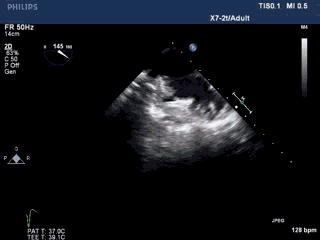

术前准备——TEE评价左心耳结构

左心耳呈多分叶状,口部梳状肌发达。